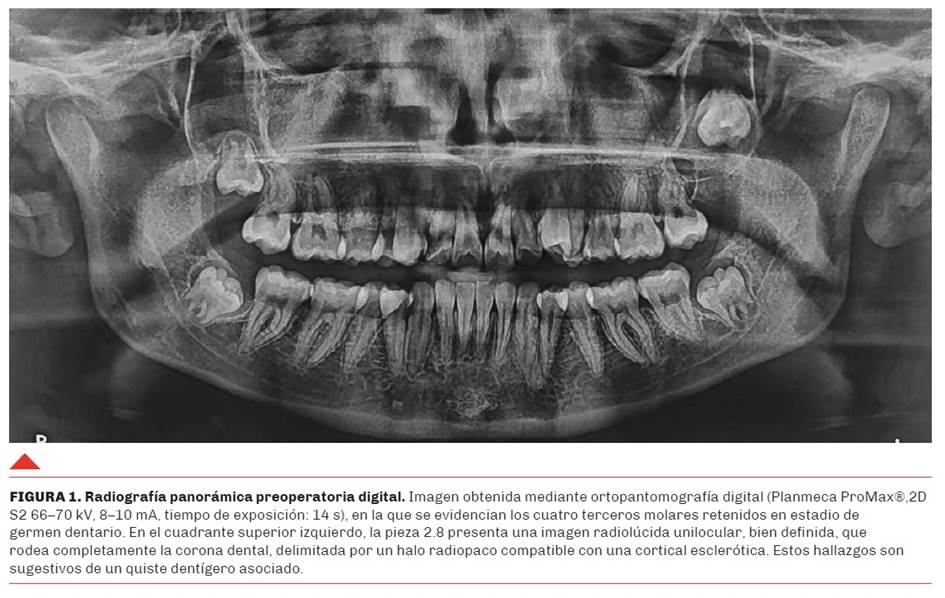

Las imágenes obtenidas presentaron limitaciones derivadas de deficiencias en la técnica de adquisición, lo que impidió una evaluación diagnóstica adecuada de la lesión en su totalidad (Figura 2). En virtud de ello, se indicó la realización de una nueva tomografía con parámetros técnicos optimizados, orientada a una caracterización precisa de la morfología y extensión de la lesión. Sin embargo, no se tuvo acceso al nuevo estudio solicitado, lo que limitó el seguimiento imagenológico completo del caso.